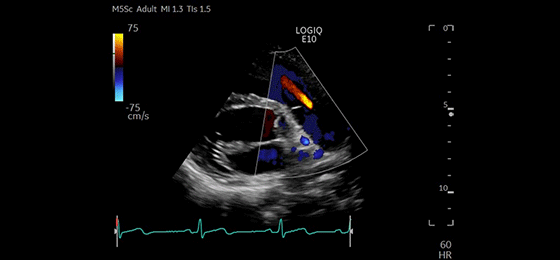

Color Through Pulmonic Valve, M5Sc-D